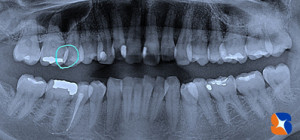

コラム「レントゲンで虫歯を説明されてもよく分からない」の画像